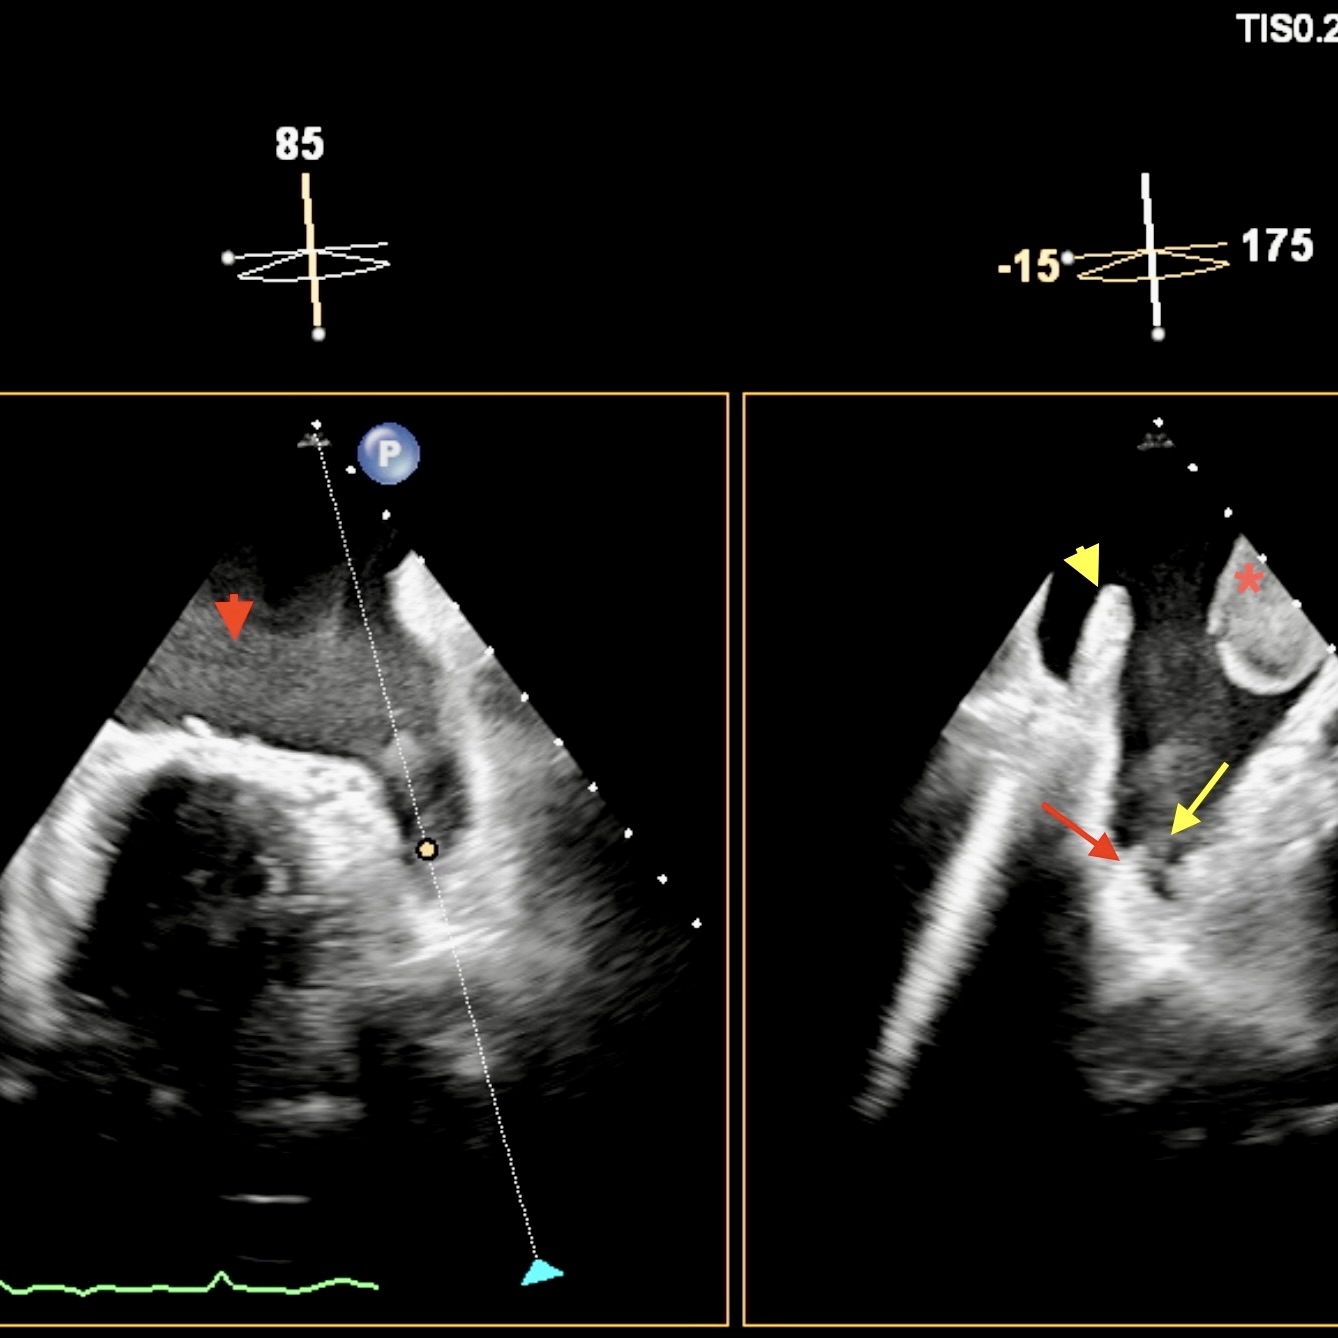

A recent case control study looking at rates of glaucomatous visual field progression before and after the onset of atrial fibrillation found important outcomes for us to consider.

Longitudinal results and meta-analyses found a significant change in visual fields following a diagnosis of atrial fibrillation. The increased progression rates post-onset are most likely linked to micro-thrombi leading to compromised ocular perfusion and ischemia. Additional risk factors include older age, hypertension, and diabetes.

These findings have important clinical implications for us, suggesting early detection and management of atrial fibrillation may help preserve visual function with our glaucoma patients. Perhaps more frequent visual field testing and OCT imaging is now justified, including our glaucoma suspects. We are also reminded of the importance to provide a multidisciplinary approach when managing individuals with or at risk of atrial fibrillation.